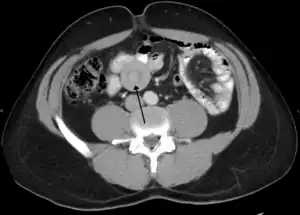

| An intussusception as seen on CT | |

An intussusception is often suspected based on history and physical exam, including observation of Dance's sign. A digital rectal examination is particularly helpful in children, as part of the intussusceptum may be felt by the finger. A definite diagnosis often requires confirmation by diagnostic imaging modalities. Ultrasound is the imaging modality of choice for diagnosis and exclusion of intussusception, due to its high accuracy and lack of radiation. The appearance of target sign (also called "doughnut sign" on a sonograph, usually around 3 cm in diameter, confirms the diagnosis. The image seen on transverse sonography or computed tomography is that of a doughnut shape, created by the hyperechoic central core of bowel and mesentery surrounded by the hypoechoic outer edematous bowel.[11] In longitudinal imaging, intussusception resembles a sandwich.[11] It is also called "pseudokidney" sign because hyperechoic tubular centre is covered by a hypoechoic rim producing a kidney-like appearance.[12]